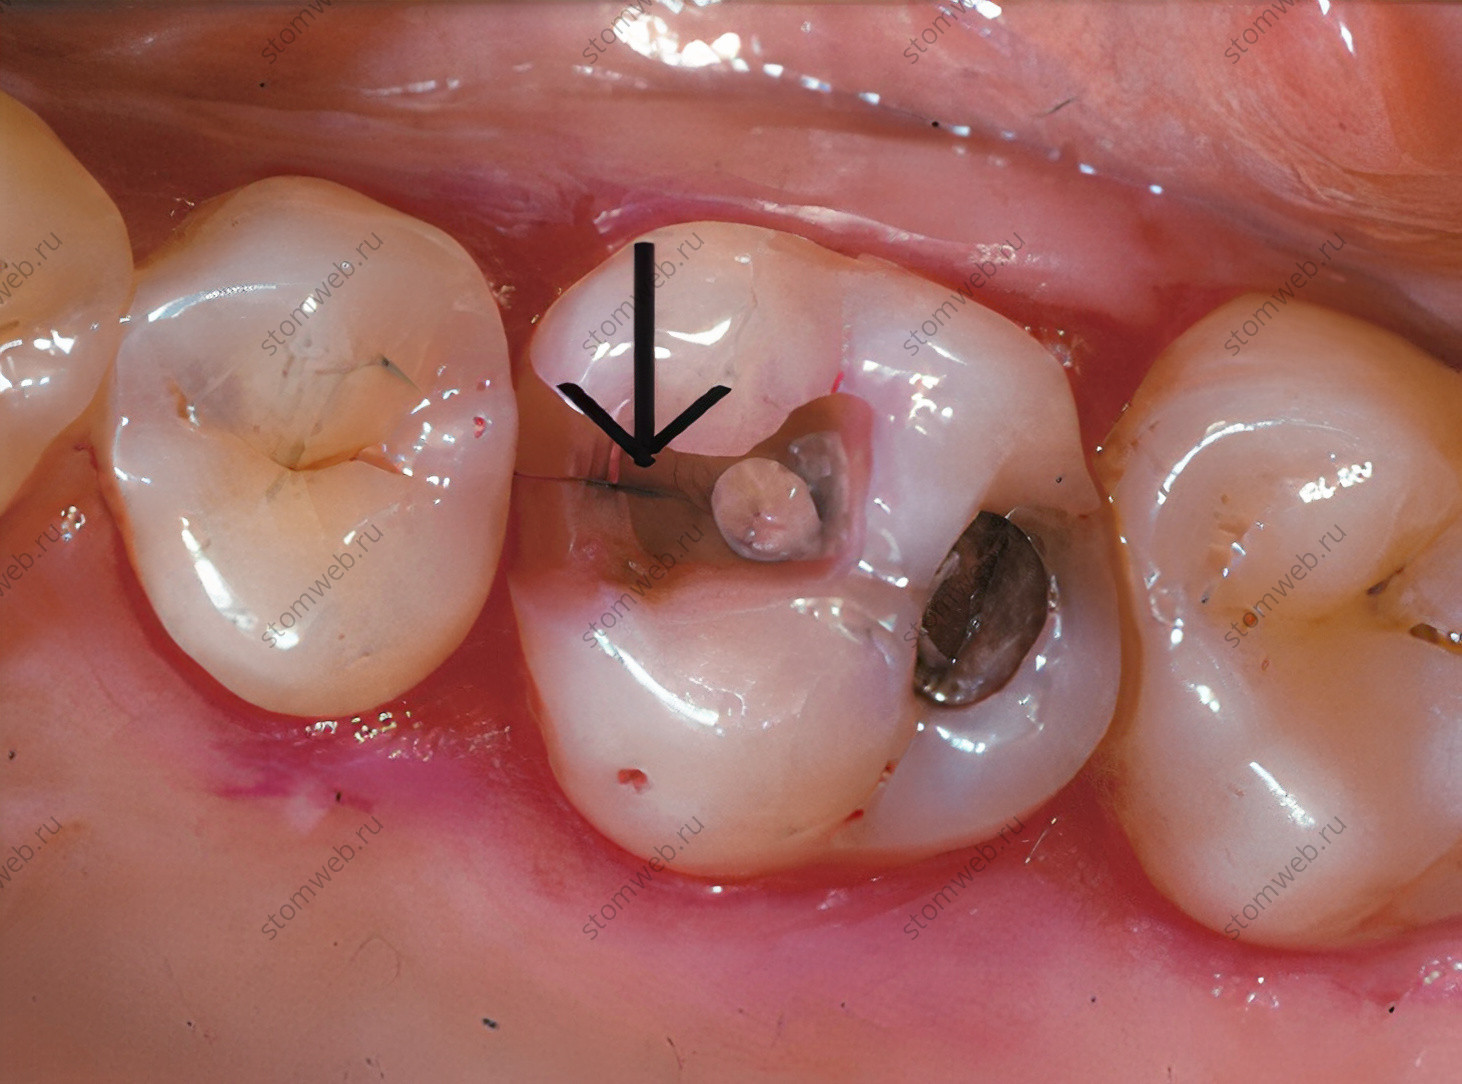

Два других термина представляют собой крайние значения переломов коронок. Линии трещин - это видимые трещины, затрагивающие только эмаль (рис. 5). Они могут распространяться на нижележащий дентин, но это обычно трудно определить. Они не связаны с симптомами, и лечение ведется по эстетическим показаниям. Другая крайность - это полный перелом зуба, который проходит через оба краевых гребня, обычно в мезио-дистальном направлении, полностью разделяя зуб на два отдельных сегмента (рис. 6). Для удобства в этой главе термин «перелом» обычно используется для различных переломов коронок.

Рисунок 6. Премоляр верхней челюсти с мезиодистальным расколом